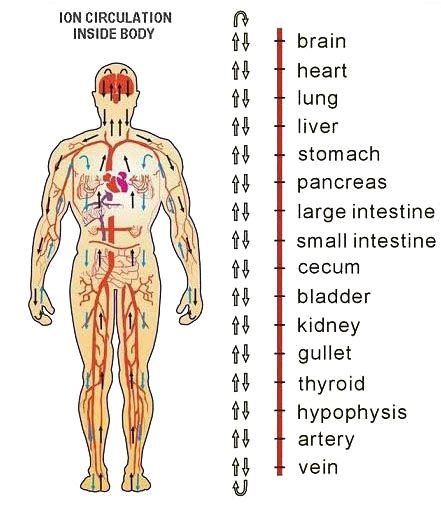

Application of Focused Ultrasound Waves stimulates connective tissue of mucous membrane to regenerate.

The apparatus therapeutic effect is based on thermal effects enabling focused ultrasound waves to precisely target tissue and the depth NOT impairing any structures through which they travel. Transformation of HIFU waves energies into thermal energies achieves therapeutic effects which are exclusively NON-ABLATIVE and BIOSTIMULATIVE enabling the treatment to stimulateneosynthesis of collagen and its regeneration and reorganisation. It also encourages neovascularization of the treated area.

In recent years HIFU technology has been successfully applied in treatments of vaginal relaxation (VRS) and stress incontinence (SUI). Precise application of HIFU waves to vaginal walls at a depth of 3 to 4.5mm warms submucosa and mucous membrane to 65⁰C. This method practically instigates connective tissue of mucous membrane to regenerate. The treatment results in higher numbers of stronger, remodeled and narrowed collagen fibers which permeate and provide strength of vaginal walls. In addition, biostimulative effects of HIFU wave initiated regenerative processes have positive impacts on the elastic fibers of mucosa and pelvic muscles. Final results of the treatment are reflected by a narrowed vaginal canal with stronger, more resistant and healthier walls. All these effects are beneficial in the treatment of SUI hence why HIFU is also applied in treatments of first and second degree SUI whilst third degree SUI requires surgery. HIFU application in treatment of first and second degree SUI can significantly delay the development of third degree SUI and therefore delay or completely eliminate the need for surgical treatment.